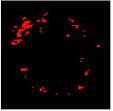

Previous studies have identified texture analysis as being useful in the analysis of ultrasound images. Plaque components appear with different texture patterns in IVUS images (Figure 11). Therefore, texture analysis methods are best suited to classifying pixels from plaque areas of IVUS images into three tissue classes, including dense calcium (DC), necrotic core (NC), and fibro-fatty (FF) [47].

Figure 11.

Different tissue types in the plaque area of IVUS images: (a) dense calcium, (b) necrotic core, and (c) fibro-fatty.